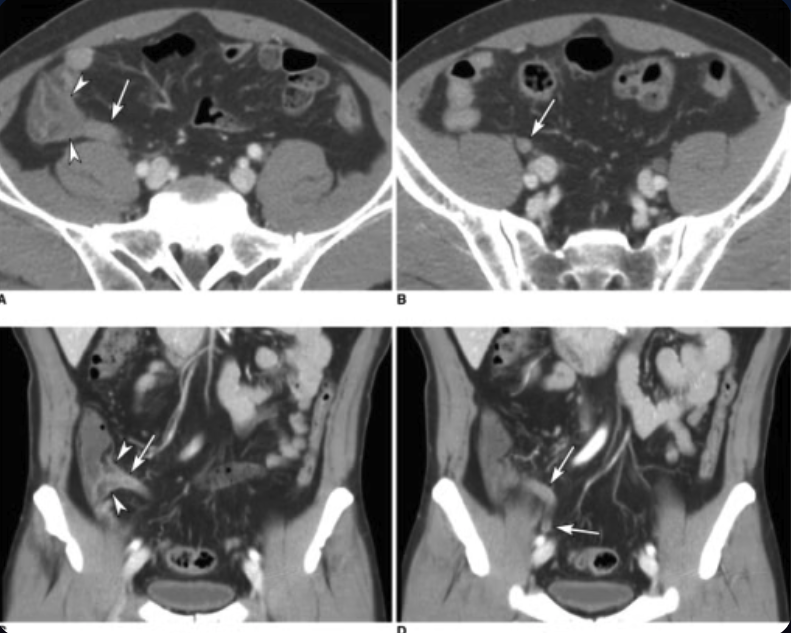

Diagnosis: Imaging - CT Scan

Purpose

Provides detailed imaging and helps confirm the diagnosis of appendicitis.

Diagnostic features on CT scan

Appendix Diameter

Appendix diameter over 6 mm is considered abnormal.

Wall Thickness

Appendiceal wall thickness over 3 mm (target sign) indicates inflammation.

Periappendiceal Inflammation

Fat stranding around the appendix is a sign of inflammation.

Faecolith

Presence of a faecolith can be seen on CT.

Cecal Changes

Thickened cecum funnelling contrast into the appendix can be observed.

CT scans in a 53-year-old man with abdominal pain. Transverse CT scans (A, B) and coronal reformation (C, D) obtained with intravenous contrast material show the thickened appendix (arrows) and oedema in cecum (arrowheads) at the orifice of the appendix. At surgery, an inflamed appendix was identified and removed.